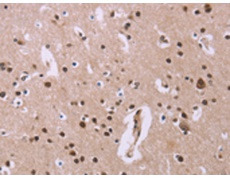

IHC positive control: |

Human brain |